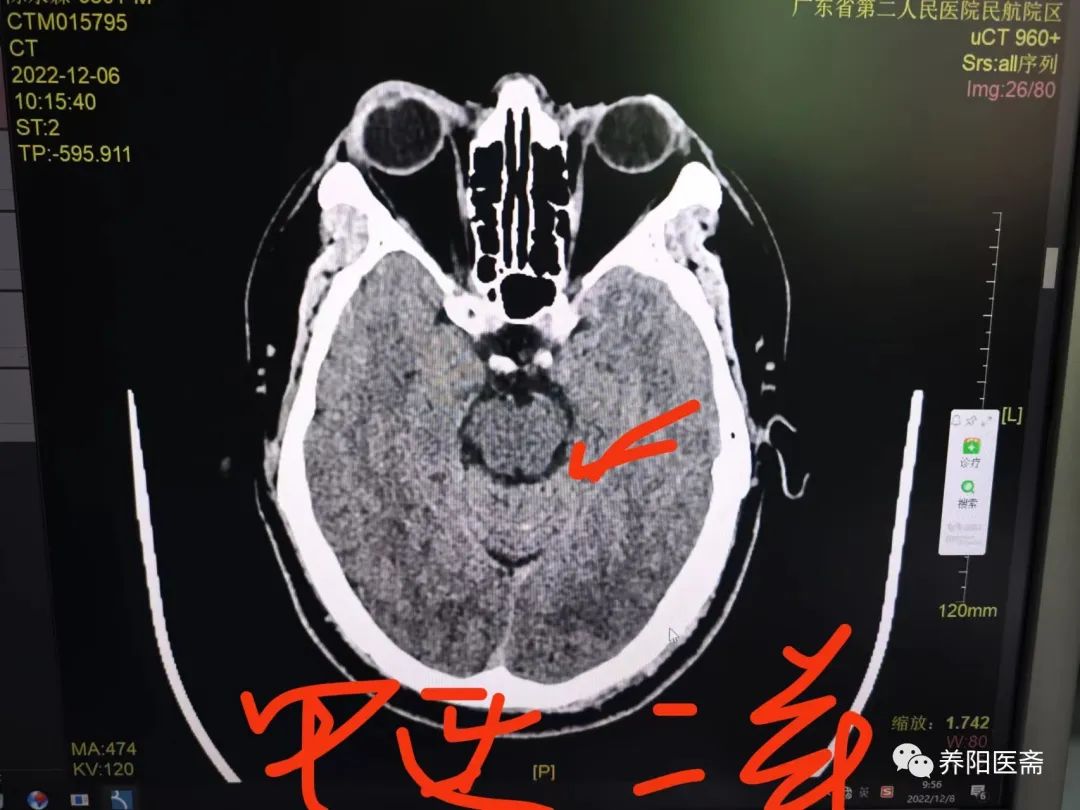

12.6日复查

复查结果显示,出血病灶较前明显吸收。